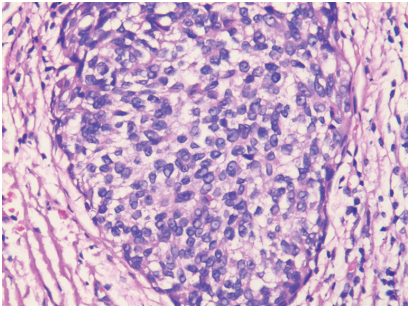

图2 部分瘤细胞呈巢状排列,细胞圆形、椭圆形,胞浆空

泡状HE染色 ×200

Figure 2 Partial tumor cells were round and oval with

vacuolated cytoplasm and in nest arrangement (H &E stain,×200)

肿物切除术”,术中完整切除红色肿物,送病理检查。标本经10%福尔马林固定,常规石蜡包埋切片,HE染色。光镜下见部分瘤细胞小片状及巢状排列,细胞呈圆形或多边形,部分瘤细胞呈胞浆空泡状的气球样细胞(图2),边界清楚,胞浆中等,核大,核仁明显。部分肿瘤细胞呈梭形,交错排列,核梭形或卵圆形(图3)。免疫组化S-100(+)、HMB45(+)、CK(−) (图4)、Vimentin(+)、EMA(−)、Ki-67阳性指数约40%。病理诊断为左眼上睑无色素性黑色素瘤,切缘未见肿瘤细胞。术后随访1年余,未见肿瘤复发。